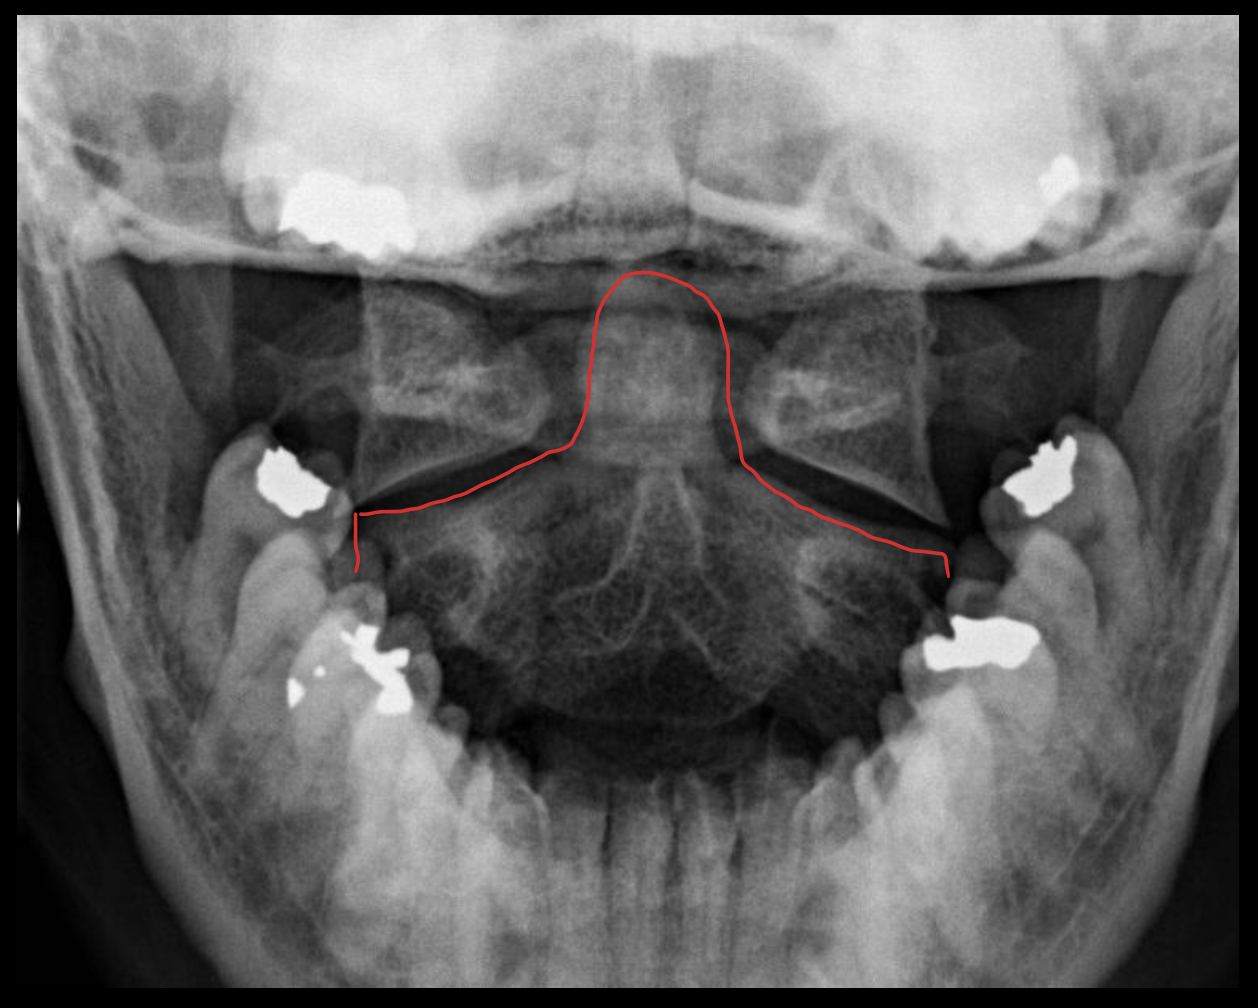

齿状突(枢椎齿突)

Odontoid

C2